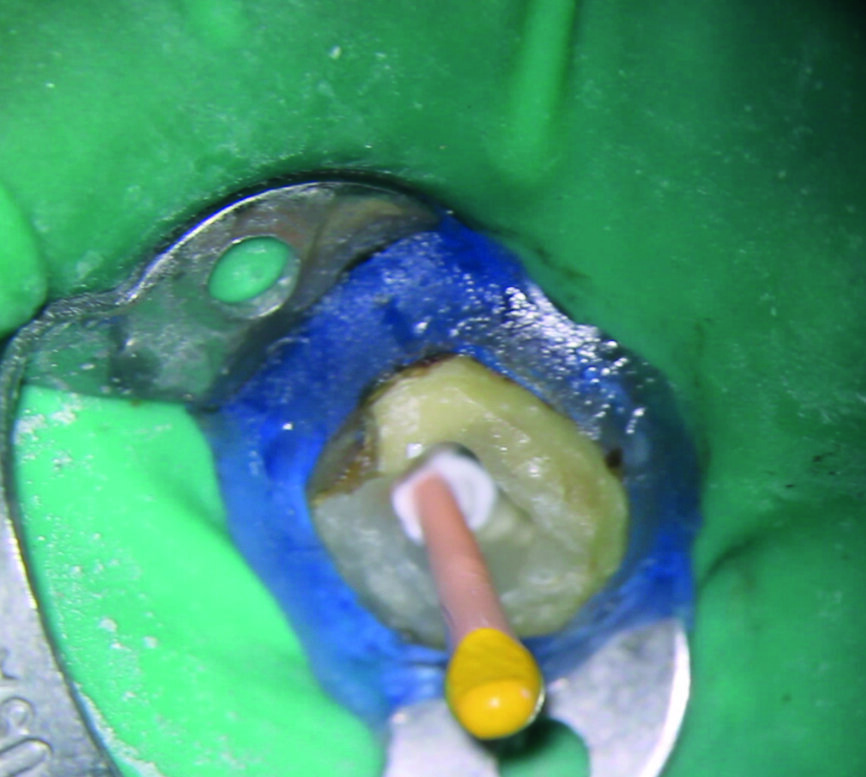

Une femme de 44 ans, sans antécédents médicaux particuliers, nous est adressée pour le retraitement endodontique de sa première molaire inférieure gauche qui cause une douleur depuis une semaine. La dent est très sensible à la percussion, ne présente aucune mobilité, et le résultat du sondage parodontal se situe dans les limites physiologiques. Une première radiographie est prise (Fig. 1). Elle montre trois fragments d’instruments fracturés demeurés dans deux canaux (mésial et distal) après le traitement endodontique précédent, ainsi que des signes d’une pathologie péri-apicale. Les résultats des examens cliniques et radiographiques conduisent à un diagnostic de parodontite apicale symptomatique de la dent déjà traitée et suggèrent la nécessité d’un retraitement.

Fig. 1 : Radiographie initiale.

Fig. 4 : Création d’une plate-forme de travail avec une fraise Gates–Glidden modifiée de taille 3.

Fig. 5 : Radiographie après retrait de la partie coronaire de gutta-percha et création d’une plate-forme de travail